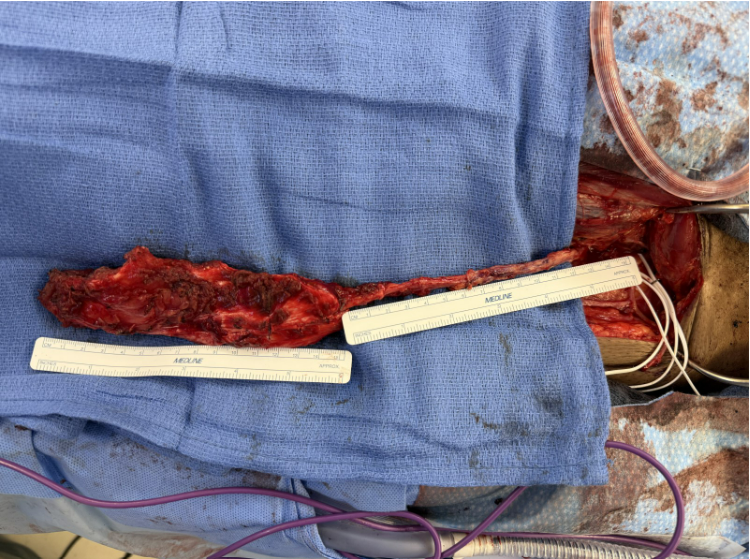

Surgeon’s view of anterolateral thigh flap (muscle-only) that was harvested for reconstruction of the patient’s cranial base defect after endoscopic resection and debridement of the infected bone from the skull base. Source: NYU Langone Health.

At that time, Dr. Pinheiro Neto discussed endoscopic endonasal cranial base resection to debride the infected bone from the skull base, followed by reconstruction of the cranial base defect with an anterolateral thigh (ALT) free flap. Chandra Sen, MD, the Bergman Family Professor of Skull Base Surgery in the Department of Neurosurgery, and Lindsey E. Moses, MD, a clinical assistant professor of otolaryngology—head and neck surgery, collaborated on the case.

To address the infection prior to reconstruction, the team performed an endoscopic endonasal approach to the ventral skull, including total ethmoidectomy, sphenoidotomies, posterior septectomy, right medial maxillectomy, and midline nasopharyngectomy. They also performed a partial clivectomy for resection of the infectious process involving the clivus and left petroclival junction.